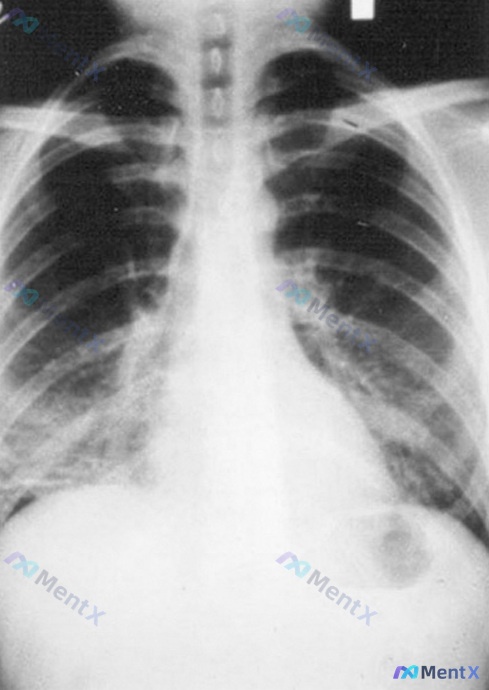

网上看到一个比较典型的青年急危重症病例线索,先放出来大家聊聊: 基本情况:男,25岁 核心表现:高热、咳嗽、呼吸困难,病程2天 现有影像:胸部X射线提示「大片实变影」 这次想先不直接问诊断,而是先挖一个临床中很容易一带而过,但其实决定了病情严重度分层的问题—— > 就这份资料里的“大片实变影”,你觉...